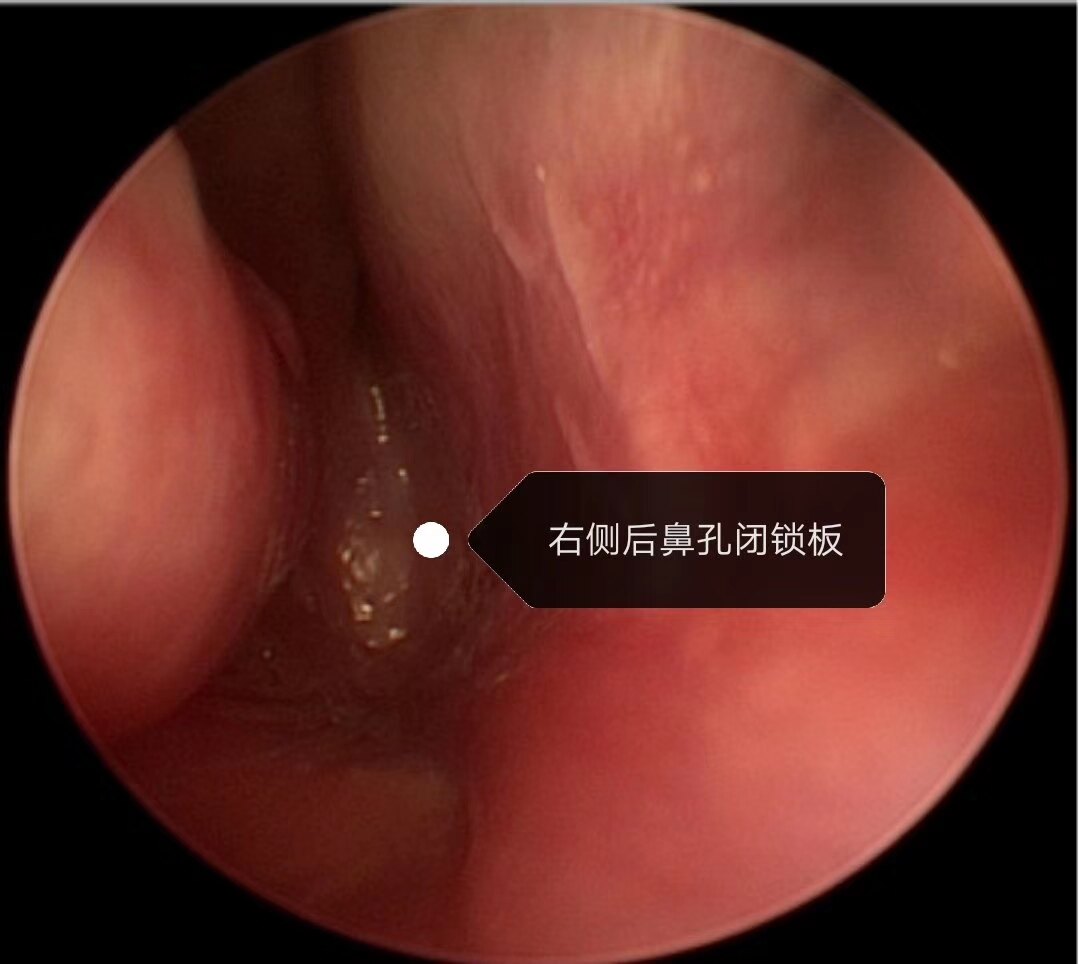

术后随访 后鼻孔成形效果良好,未出现再次狭窄和闭锁,一次手术成功